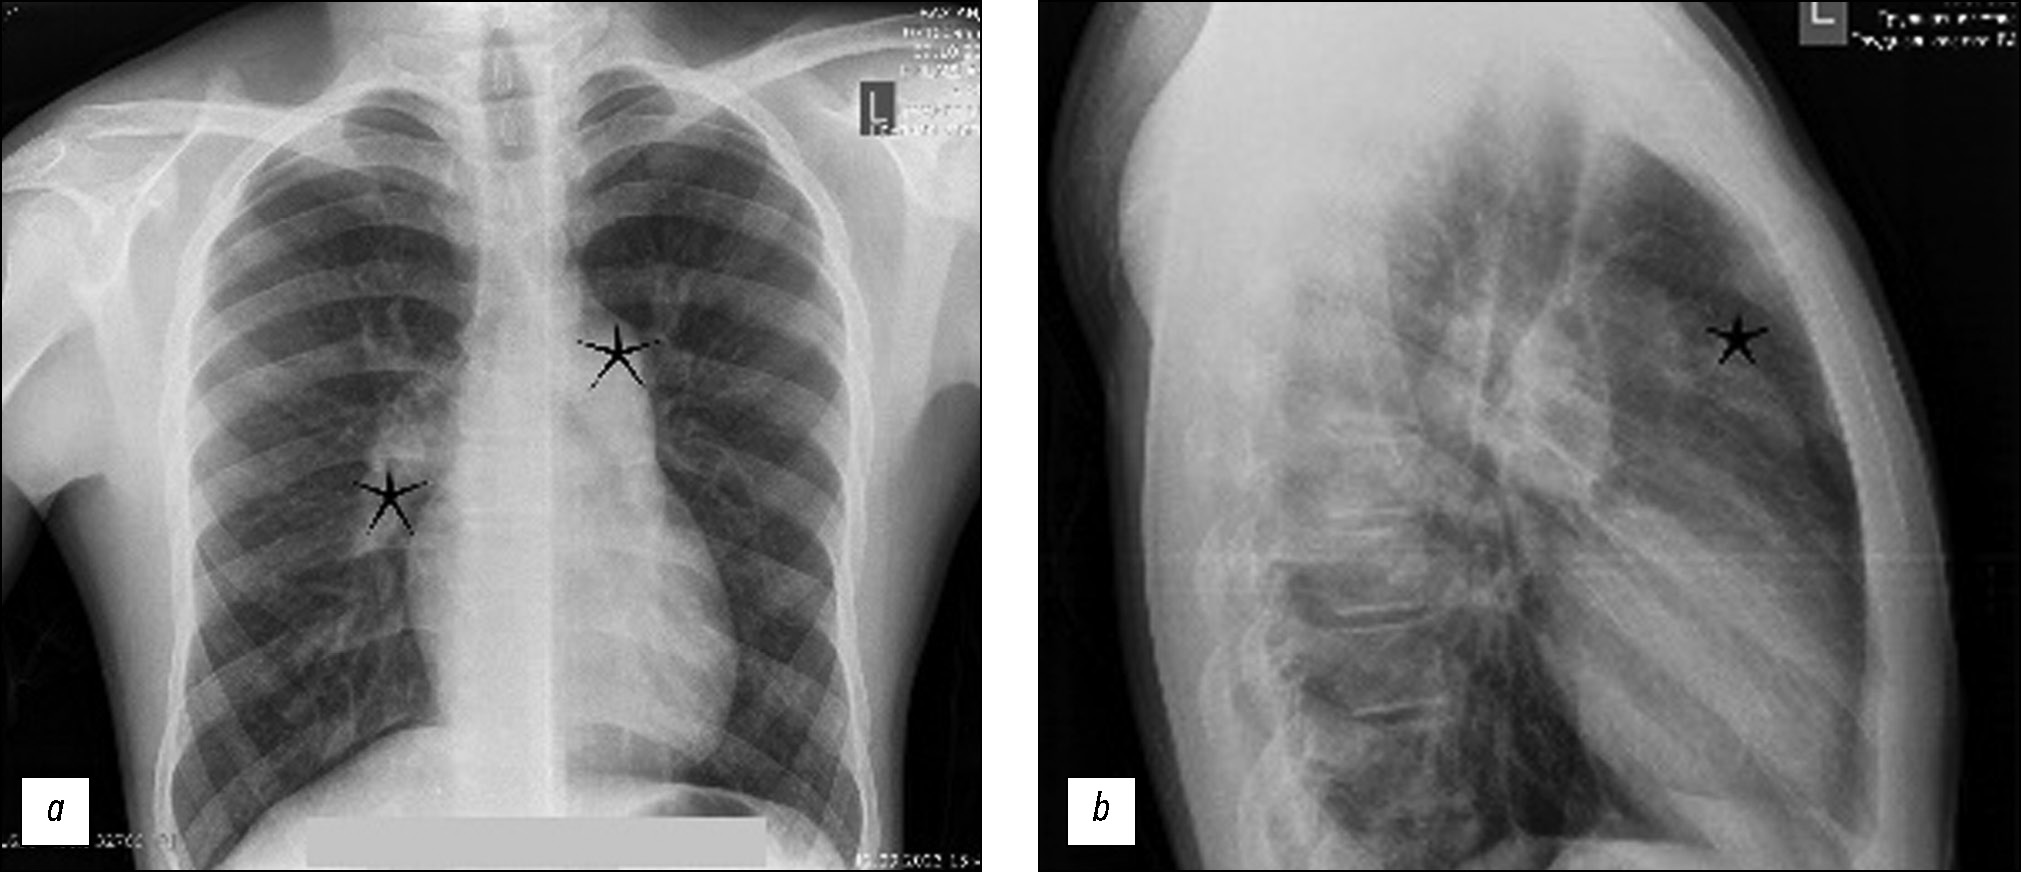

Pulmonary artery aneurysms and pseudoaneurysms are uncommon anomalies; however, their associated morbidity underscores the importance of recognizing them. Herein, we present a clinical case involving a 15-year-old male patient who presented at our clinic with complaints of hemoptysis. Upon diagnosis, a left lung aneurysm was found. Subsequent computed tomography angiography and intervention on the pulmonary arteries confirmed the presence of pulmonary artery aneurysms, elucidating that the hemoptysis was caused by the rupture of the aneurysm. The intervention on the pulmonary artery further confirmed the diagnosis. Early detection and management of pulmonary artery aneurysms are crucial, particularly in young patients, as timely intervention can prevent severe complications and improve patient outcomes. Raising awareness of these vascular abnormalities and promptly addressing them through appropriate diagnostic measures and interventions can help healthcare providers effectively mitigate the potential risks associated with pulmonary artery aneurysms, thereby enhancing patient care and prognosis.